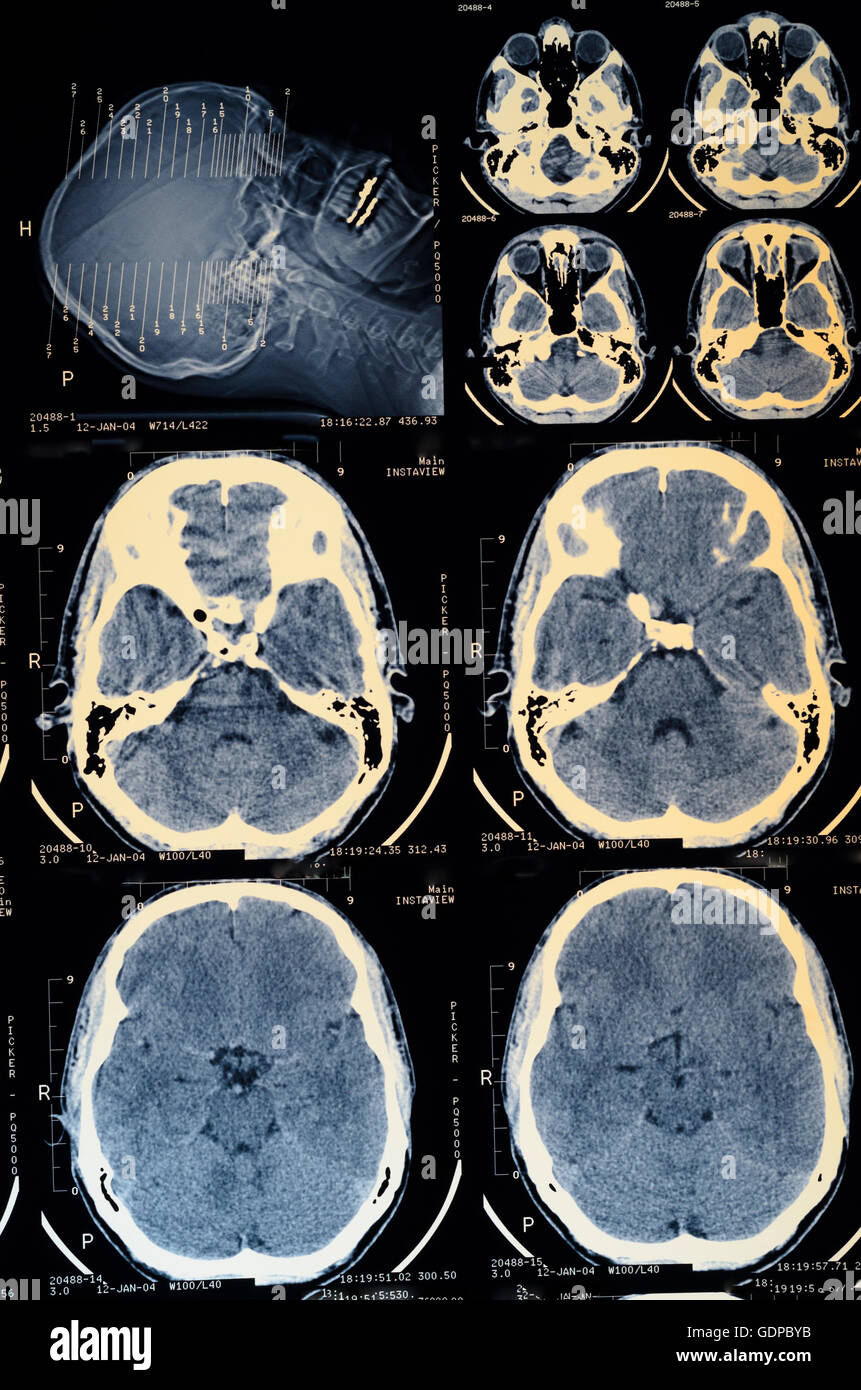

: Imagerie par résonance magnétique ( IRM ) : des images transversales de la tête , les yeux remplis de dents, l'amalgame, cerveau, , ,